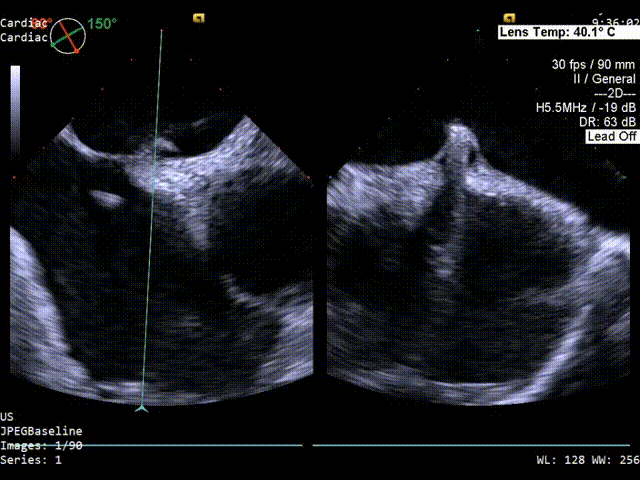

术前发泡实验超声影像

主动脉短轴切面超声影像

双房切面超声影像

静息状态下房水平见左向右分流。

color超声影像

原发隔厚度0.84mm,继发隔厚度约:5mm;

PFO间隙2mm,隧道长度8.2mm(主动脉短轴);

隧道长度14mm(双房切面);

1、PFO结构:静息状态下房水平见左向右分流。继发隔厚约5mm;原发隔厚约0.84mm;未探及下腔静脉残瓣及希阿里氏网。

2、PFO参数:隧道裂隙宽约2mm;卵圆孔隧道长度8.2mm(主动脉短轴)14.6mm(双房切面)。